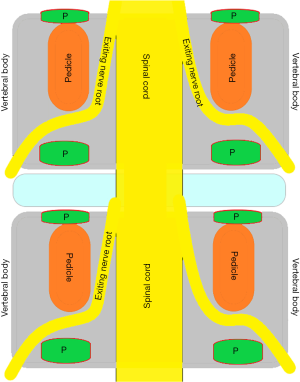

To investigate fully radiographic anatomy of PETOFPC, the authors chose to measure the distances from the posterior corner (P point, Figure 1) in lumbar spine to the corresponding targets.

Posterior corner in lumbar spine was selected as the screw entry point (P point) for oblique fixation. The screw entry point (P point) in posterior-inferior corner is the bony area between the upper margin of the pedicle and the upper endplate. The screw entry point (P point) in posterior-superior corner is the bony area between the lower margin of the pedicle and the lower endplate (Figure 2). The corresponding targets are A, B, C, D, E, and F, respectively (A: the middle point of the contralateral anterior-middle 1/3, B: the contralateral anterior-middle point, C: the middle point of the contralateral side, D: the upper point of contralateral anterior-middle 1/3, E: the contralateral anterior-upper point, F: the middle-upper point of the contralateral side) in the contralateral anterior region (Figure 3).

PETOFPC technique innovatively sets screws from posterior corner in lumbar spine in a regular 7.5-mm diameter channel. PETOFPC is also performed in the posterolateral transforaminal approach (Figure 18). A cylindrical sheath with an outer diameter of 7.5 mm were inserted in sequence. Through the sheath alone or the endoscope, the intervertebral disk and cartilaginous endplate were removed while confirming through percutaneous endoscopic observation that no cartilage remained. At the completion of the endplate preparation, the new integrated fixable and fused interbody cage was inserted into the intervertebral space (16). Before the new integrated fixable and fused interbody cages were expanded, we should clearly expose the screw entry point in posterior corner. The screw entry point is the bony area between the pedicle and the endplate. When intervertebral height was restored, the two wings of new integrated fixable and fused interbody cage splay to the sides and fit to posterior corner in lumbar spine (Figure 19). In the single 7.5-mm channel, endoscopic visualization was used to monitor placing screws to make the new integrated fixable and fused interbody cage fixed in lumbar spine. The angles of screw placement were made up of inward inclined angle, head tilt angle and tail tilt angle, namely c1, c2, c3, a1, a2, a3, b1, b2 and b3, all which was measured and analyzed in this study.